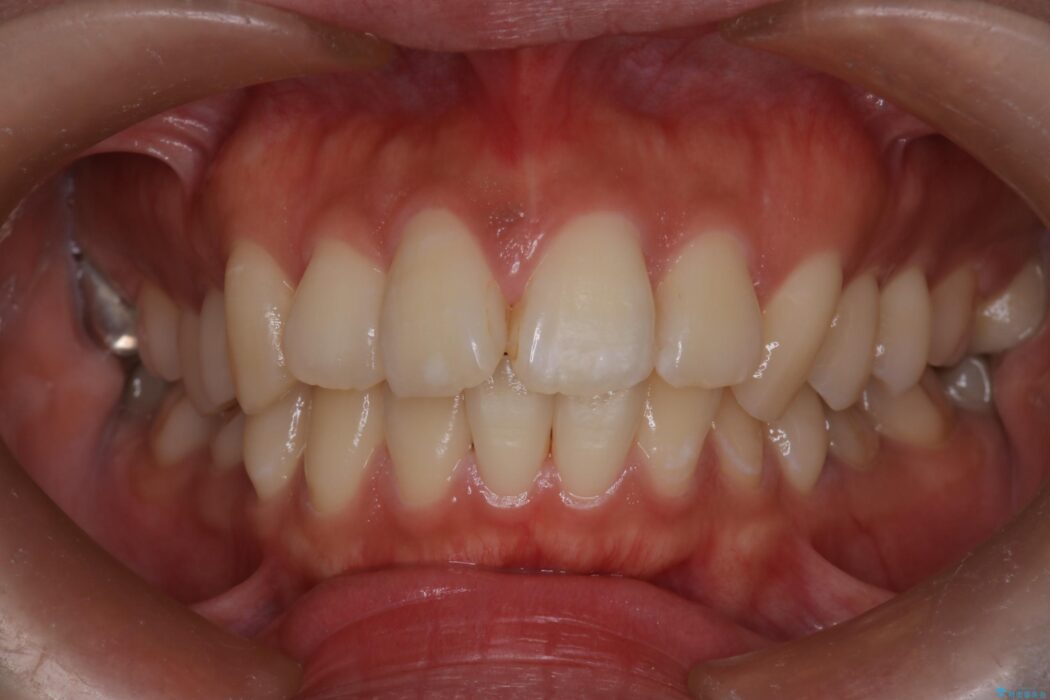

治療後について

小臼歯の抜歯矯正により口元をきれいに改善することができました。

口ゴボではなくなり、すっきりとした口元になり患者様にも満足していただけました。